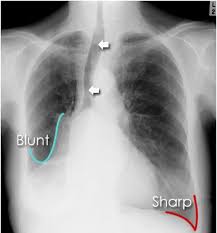

Approximate pleural effusion volume on chest X-ray (upright PA) — rough reference (Written February 23, 2026)